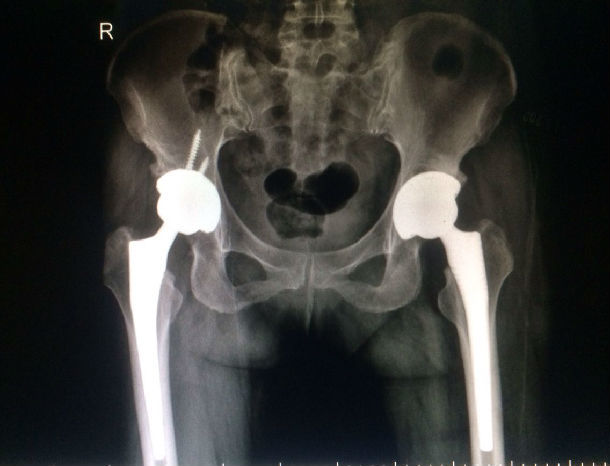

一例双侧股骨头坏死人工陶瓷全髋关节置换分享